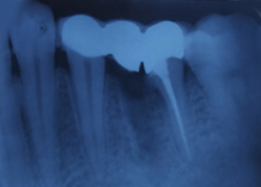

Prosthesis Cementation (Bridge)

Radiograph with Prosthesis (8 Months)